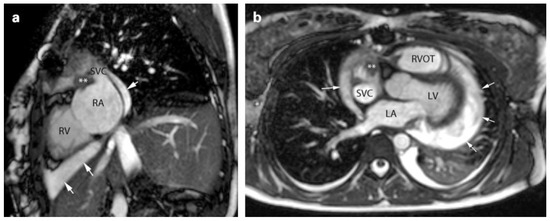

Cardiac Sarcoma in a Teenager

by Rahel U. Soyka, Emanuela R. Valsangiacomo Büchel, Eva Bergsträsser, Peter K. Bode, Martin Schweiger and Anna Cavigelli-Brunner

Primary cardiac sarcomas are very rare and the prognosis is poor with a reported survival of usually less than one year after diagnosis. There is few data available for therapy recommendations and outcome. We present the case of a 16 year old patient [...] Read more.

Primary cardiac sarcomas are very rare and the prognosis is poor with a reported survival of usually less than one year after diagnosis. There is few data available for therapy recommendations and outcome. We present the case of a 16 year old patient with a solitary angiosarcoma situated in the right atrium. A complete resection was followed by chemotherapy. Follow up more than 5 years after the initial diagnosis was uneventful with no signs of tumor recurrence. Epidemiology, diagnosis, treatment, follow up and prognosis of cardiac sarcoma are discussed. Full article